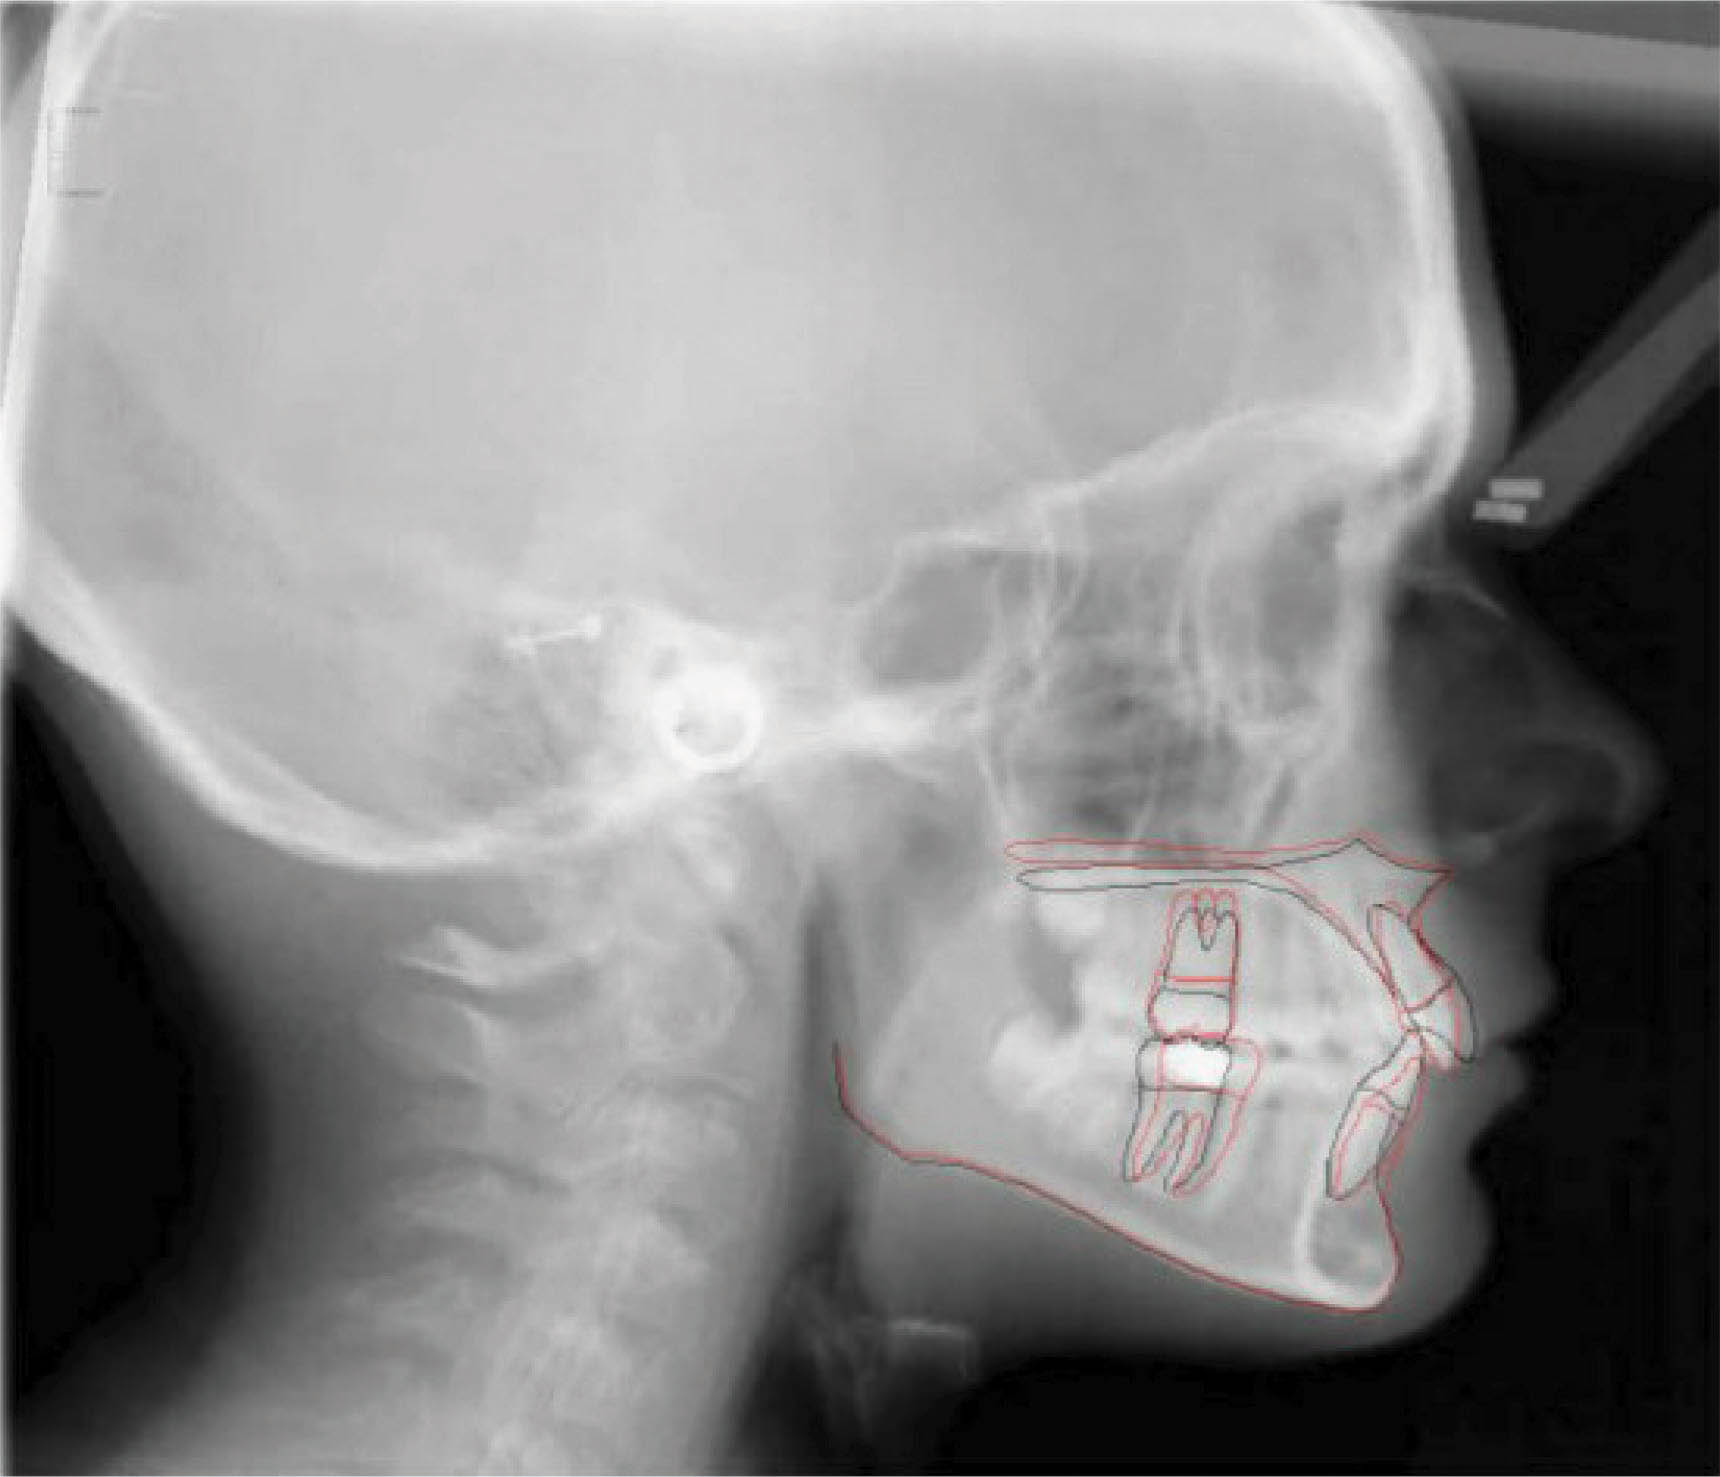

بیمار بعدی یک دختر ۱۲ ساله با اکلوژن ClII/1 و دیپ بایت است. فضا بین قدامیهای بالا و کرادینگ قدام پایین مشخص است. عکس OPG طبیعی است. لترال سفالومتری نشان دهنده رابطه کلاسII فکی و افزایش جزئی در ارتفاع صورت است (شکلهای 98-۶ الی 100-۶). به میزان زیاد لثه در زمان لبخند دقت کنید. چک لیست او به شرح زیر است:

شکل 98-6

شکل 99-6

شکل 100-6

الاستیک کلاسII برای این کودک در حال رشد تجویز گردید. برای کاهش میزان لثه در گامی اسمایل اینتروژن مطلق سانترالهای بالا در نظر گرفته شده است. برای اصلاح کرو اسپی، اینتروژن قدام پایین هم انجام شد. اکستروژن خلف برای اصلاح دیپ بایت صحیح نمیباشد چون ارتفاع عمودی صورت کمی بیشتر از نرمال است.

در عکسهای پایان کار (شکلهای 101-۶ الی 103-۶) اصلاح اکلوژن کلاسII، اوربایت و اورجت طبیعی، و دندانهای مرتب مشخص هستند. مقایسه تصاویر قبل و بعد (شکلهای 104-۶ و 105-۶) نشاندهنده کم شدن گامی اسمایل بیمار است که خود شاهدی بر اینتروژن مطلق انسیزورهای بالا میباشد. عکس نهایی OPG طبیعی است و سوپر ایمپوز نمودن عکسهای لترال سفالومتری نشاندهنده ثابت ماندن موقعیت ۶ بالا و کنترل خوب روی پلن مندیبل است.

نتیجه: درمان ۲۸ ماه به طول انجامید، و ۲ قالبگیری مجدد داشتیم و از الاستیک کلاسII ۲ انسی استفاده شد.